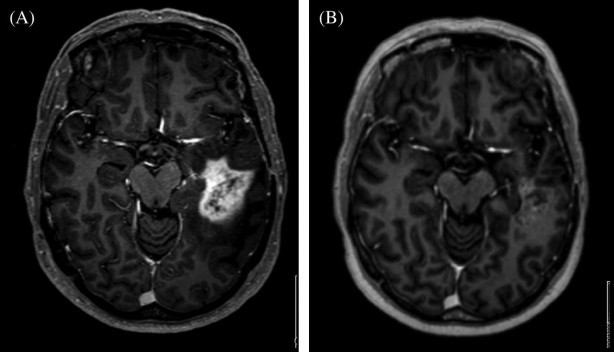

İngiltere merkezli Imperial College London'ın bir parçası olan Beyin Tümörü Araştırma Mükemmeliyet Merkezi tarafından yapılan araştırmalar, standart kan örnekleriyle hastalığın izlerini tespit edebildiklerini ortaya çıkardı.

Uzmanlar, bu yöntemin, çoğu beyin tümörünü teşhis etmek için kullanılan riskli cerrahi ihtiyacını azaltırken teşhis ve tedaviyi hızlandırabileceğini söylüyor.

Kullanılan "sıvı biyopsi"nin özellikle erişilemeyen beyin tümörleri olan hastalar için faydalı olacağını, böylece tedaviye mümkün olan en kısa sürede başlayabileceklerini söylediler.

Uluslararası Kanser Dergisi'nde yayınlanan bulguların önemli olduğunu söyleyen araştırmacılar, glioblastomalı hastaların yüzde 1'inden azının on yıldan fazla yaşadığını ve erken teşhisin önemli olduğunu kaydettiler.